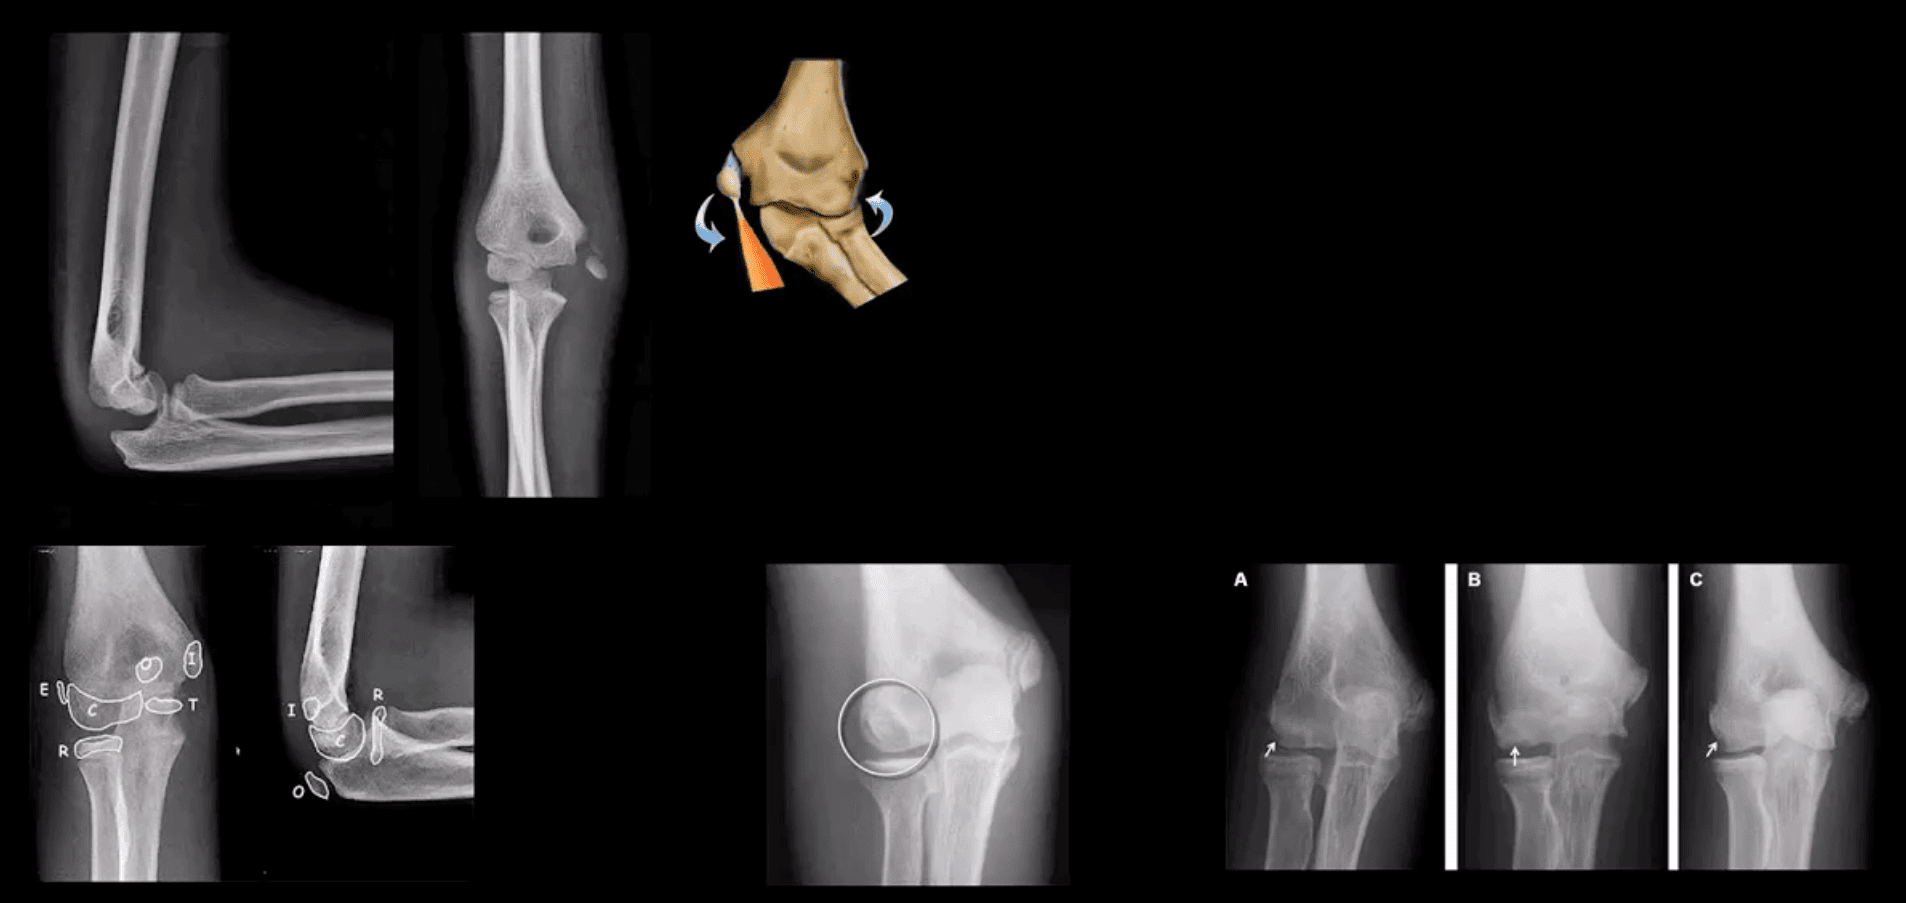

- Radial head (RH) Fx: Mason classification helps to determine the degree of complexity and mode of treatment

- Type 1- undisplaced is the m/c and stable contained by ligaments. On radiographs can be very subtle and evaluation of abnormal elbow fat pads is critical and often the only diagnostic clue

- Type 2- displaced by 2-mm or > with rotational block

- Type 3- comminuted >2-3 fragments and

- Type4 is presented with RH fx, posterior elbow dislocation and sometimes Coronoid process fracture often d/t Brachialis M avulsion

- Note abnormally displaced anterior fat pad (orange arrow) and the emergence of the posterior fat pad (green arrow) that is usually deep in the olecranon fossa and not seen unless acute hemarthrosis or other effusiondevelopsFat pad signs are most reliable indicators of intra-articular elbow Fx

- Mason type 1 RH Fx can be v. subtle and missed. Radiographic search should involve a

close evaluation of positive fat pad signs. Note anterior fat pad displacement aka Sail sign and the presence of the post fat pad d/t acute bleed

- Supracondylar Fx: this is the M/C elbow Fx in children.

- Especially, the un-displaced types 1(top right) is difficult to Dx. Abnormality of “fat pads” and anterior humeral line and radiocapitella line disturbance are often most reliable

- Epicondyle Fx: common pediatric injury, about 10%.Essentially an avulsion Fx and a MUCL tear. Medial epicondyle is m/c Fx. FOOSH is the m/c mechanism.M>F. If minimally displaced or undisplaced can be treated with casting esp. in non-dominant arm. If displaced as in this case, require ORIF.

- OCD of the Capitellum is a common athletic injury induced by repeated compression/flexion. OCD must be DDx from Panner’s disease or osteochondritis typically presented in younger patients

- Difficulty in diagnosis may stem from multipleapophysis about the elbow (see CRITOE)